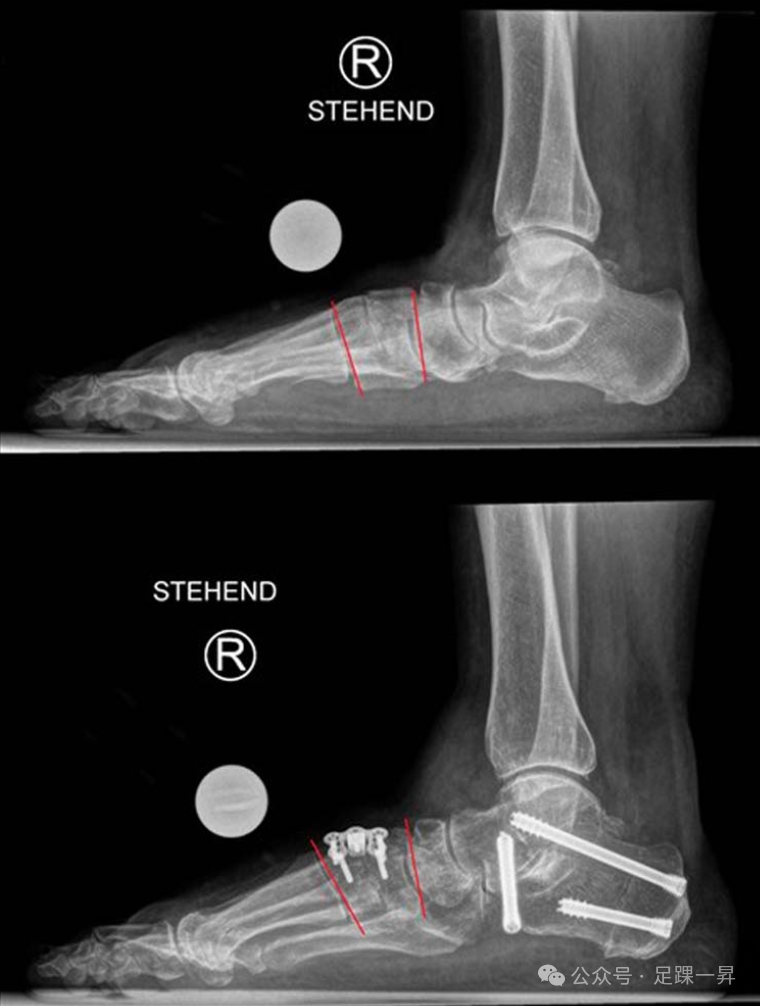

构成: 胫骨 腓骨远端 下胫腓韧带复合体 下胫腓韧带复合体 下胫腓前韧带 下胫腓后韧带 胫腓横韧带 骨间膜远端部分 骨间韧带